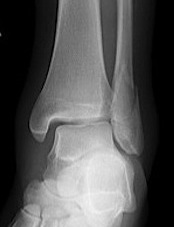

Weber A fibular fracture

Definition

Fracture below level of syndesmosis

Fibular avulsion fracture

Management

Stable

Full weight bear